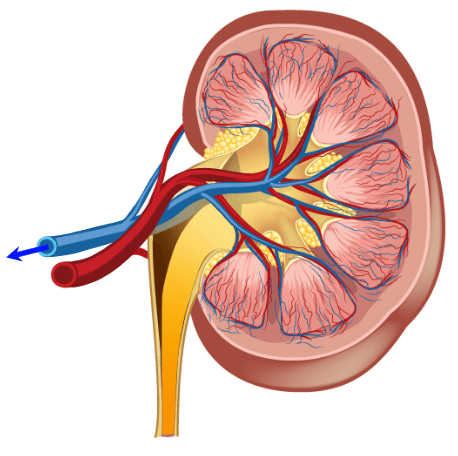

When discussing contrast agents, one must have a full appreciation of the benefits, which we have already discussed, but also the risks. The biggest risk of Gadolinium-based contrast agents is NSF or Nephrogenic systemic fibrosis. Which we will discuss in a few minutes. At present, the only measure that can predict a possible outcome of NSF is the renal function. This involves a simple blood test, which can be done in a doctor’s office or clinic, just a few minutes to a few days before the MRI. We look at the patient’s Creatinine and GFR.

Kidney Function

Kidney function is important to measure when injecting Gadolinium (and some other IV contrasts). It is imperative that the kidneys be working well enough to take the contrast agents out of the bloodstream quickly, usually within 24 hour period. When Gadolinium stays in the bloodstream too long, it will deposit in the tissue and may lead to a condition called NSF, which we will discuss later on.

The kidney function is measured with a simple blood test. The BUN or Blood Urea Nitrogen is measured This will tell how well hydrated the kidneys are. A normal range for BUN is 17-25. The next number is creatinine. The creatine tells us how well the kidney function or how efficiently they are removing excess creatine from the blood. A normal creatinine level is 0.7-1.6.

Always be sure to check the serum creatinine, not the urine creatinine which is expected to be much higher. Lastly, we evaluate the GFR or eGFR because it is estimated. The GFR is the Glomerular Filtration Rate. This number is considered to be more accurate than just a Creatinine because it takes other factors such as age, sex, and ethnicity into consideration. A normal GFR would be anything over 60. On a young healthy adult, it is around 100. Usually, about 60, a result is given>60. One would be concerned about injecting Gadolinium in a patient with a GFR less than 60, and usually, no injection occurs if it is below 30.